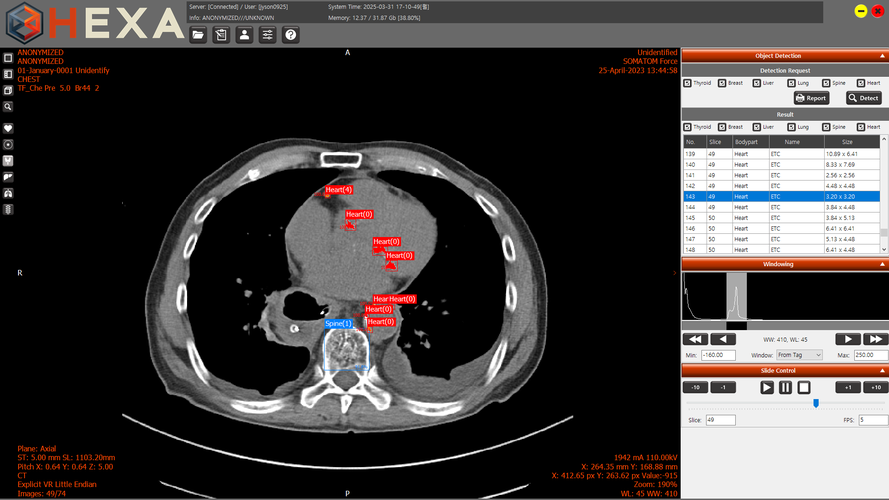

엑스큐브, 흉부 CT 기반 다장기 AI 진단보조 솔루션 'HEXA' 출시

HEXA는 한 번의 흉부 CT로 갑상선·심장·폐·간·유방·척추 등 6개 장기의 이상 의심 영역을 AI가 자동으로 표시하는 진단보조 솔루션이다. 기존에는 주된 질환 위주 판독 과정에서 다른 장기의 소견이 간과되는 경우가 있었으나, HEXA는 이러한 누락 가능성을 줄이는 데 초점을 맞추고 있다.

또한 CT 영상 수신 후 자동으로 분석을 실행하는 AutoRun 기반 워크플로우와, 병명을 제시하지 않고 시각적 표시만 제공해 임상의 판단을 존중하는 진단보조 UI를 갖추고 있다. 기존 CT 데이터를 재활용해 이상 소견을 추가 확인할 수 있는 데이터 기반 안전망 구조도 특징이다.

HEXA:BASE는 기본 뷰어 기능을 제공하는 1등급 의료기기로, KTL 시험에서 약 96%의 정확도를 확인했다. 현재 10여 개 의료기관에서 실제 판독 환경에 적용돼 사용성이 검증되고 있다. HEXA Pro는 AI 기반 자동 검출 기능을 포함한 진단보조 솔루션으로, 2등급 인허가 요건 충족을 위한 기술 고도화를 진행하고 있다.